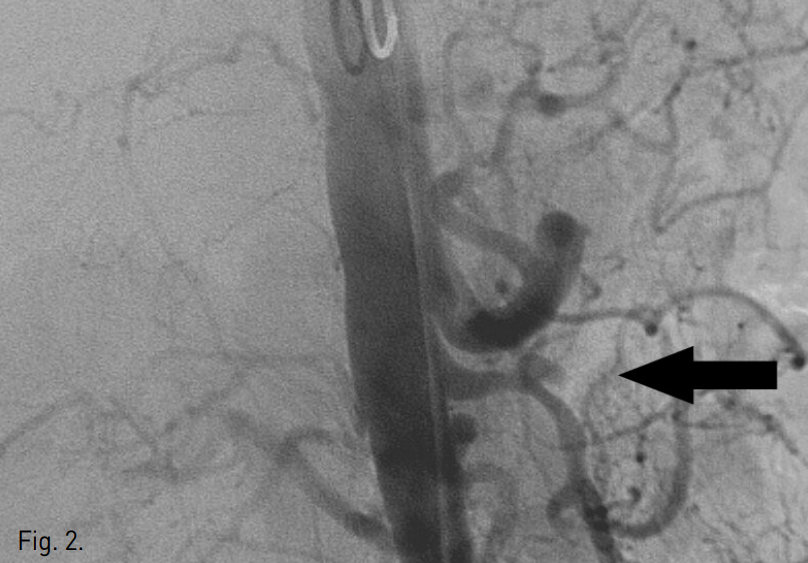

우측 대퇴동맥에 5F sheath (Terumo, Tokyo, Japan)를 삽입 후 5F pig-tail catheter (Cook, Bloomington, IN, USA)로 복부대동맥조영술을 시행하였다. 대동맥조영술상 상장간막동맥 근위부에 dissecting aneurysm이 관찰되었고 상장간막동맥은 patent하였으나 intramural hematoma로 인해 luminal narrowing 소견을 보였다(Fig. 2).

Fig. 2

Abdominal aortogram reveals a dissecting aneurysm (arrow) at proximal SMA and irregular luminal narrowing of SMA